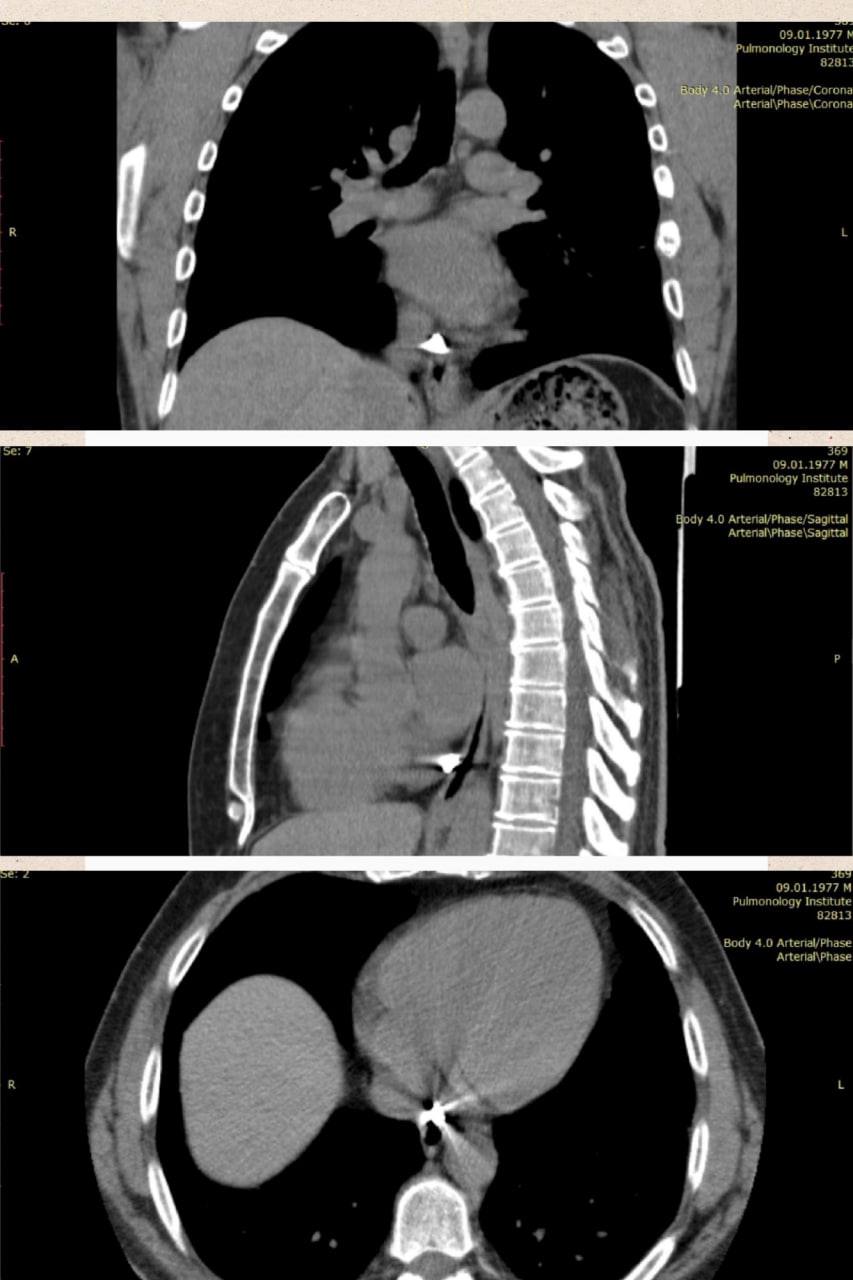

На КТ дослідженні фахівці побачили уламок значних розмірів - 8×9 мм, який застряг в перикарді (зовнішня сполучнотканинна оболонка серця - тонкий, але щільний мішок, в якому розташоване серце).

Лікарі зазначили, що дане специфічне розташування суттєво ускладнювало оперативне втручання.

Хірурги вирішили провести мініінвазивне торакоскопічне видалення металевого уламка, із застосуванням магнітного інструментарію для евакуації його з товщі тканини.

Втручання відбулось через невеликий надріз в грудній стінці.